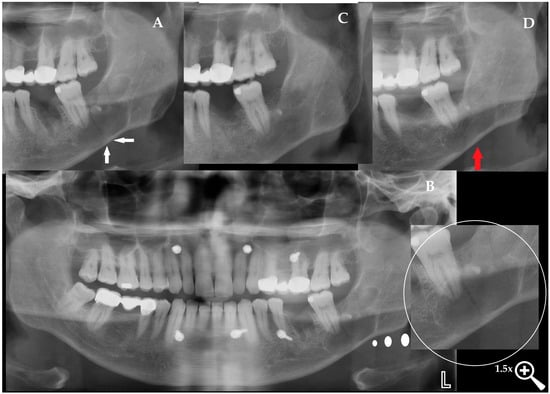

Figure 1. Radiolucent lesions of the mandible often remain unnoticed for years, silently expanding within the bone without any symptoms or visible changes [1]. In certain cases, these deceptively quiescent lesions may weaken the mandibular structure over time and predispose it to unexpected fractures, even after minor trauma [2]. Such an incidental and asymptomatic presentation was observed in the following case. A 50-year-old male patient was referred by a local radiologist following a routine dental panoramic radiograph (DPG) that revealed an incidental finding (Figure 1, white arrows shows the inferior border of the lesion). The patient was systemically healthy, with no history of endocrine disorders such as primary or secondary hyperparathyroidism; metabolic bone diseases such as Paget’s disease; or systemic conditions affecting bone metabolism, including renal osteodystrophy secondary to chronic renal failure, all of which can produce radiolucent lesions in the jaws. Clinically, the patient was asymptomatic, exhibiting no pain, swelling, abscess formation, or facial asymmetry, and no cortical expansion was detected on examination. Radiographic assessment demonstrated that the right mandibular third molar was fully erupted, whereas the left mandibular third molar was completely impacted and retained within the bone. A well-defined, corticated, unilocular pericoronal radiolucency enveloping the crown of the impacted tooth was observed, extending from the enamel–cementum junction, radiographically consistent with a dentigerous cyst. Cone-beam computed tomography (CBCT) confirmed a unilocular lesion with marked buccolingual expansion and cortical thinning in the left posterior mandible but without obvious cortical interruption or a clearly visible fracture line, and the inferior alveolar canal remained corticated and mildly displaced. Nevertheless, because clinical and radiographic findings alone are insufficient for a definitive diagnosis, histopathological evaluation was deemed necessary to confirm the nature of the lesion. Quite often, the extent of a bone lesion may be underestimated, which can lead to an iatrogenic fracture during the removal of a cyst or an impacted tooth. Additionally, a pathological mandibular fracture may occur shortly after surgery. In the present case, the lesion was treated by cyst enucleation and removal of the impacted third molar without prophylactic mandibular plating, as intraoperative mandibular stability appeared satisfactory and no crack propagation or bone bending was palpated. However, in the third postoperative week, the patient developed new-onset pain in the left mandibular region without any reported trauma, and repeat imaging revealed a non-displaced vertical fracture line extending from the distal aspect of the second molar toward the inferior border of the mandible, which was managed conservatively with intermaxillary fixation and close radiological follow-up. In such cases, several considerations should be made: improving diagnostics with CBCT; performing simultaneous preventive or prophylactic mandibular plating (PMP); using other maxillomandibular fixation devices to enhance bone stability, prevent fracture, and promote proper healing; or combining PMP with bone grafting after cyst or tooth removal to significantly reduce the likelihood of mandibular fracture [1,2,3,4]. Three-dimensional assessment of bone condition is fully achievable with CBCT, while the extent of bone loss in the mandible and the size of the three-wall bone defect might influence the use of any bone graft material with or without a PMP. On the other hand, those situations are case-dependent and vary greatly among patients. Secondly, when a standard DPG is used for fracture assessment, whether after typical trauma or following the removal of a large cyst, tumor, or impacted molar, the presence of minimally displaced fracture patterns, very narrow fracture lines, or inconclusive bone findings may lead to failure in identifying a fracture.

Figure 4. Dentigerous cysts are known to expand slowly and silently over many years, often without producing any symptoms, while progressively thinning the cortical plates to a degree that may compromise mandibular integrity. In such cases, even in the absence of pain, swelling, or functional limitation, postoperative morbidity is inherently increased. The risk of mandibular fracture has been reported both during enucleation and throughout the early postoperative period, particularly in large lesions with marked cortical attenuation, with postoperative fracture rates described in the literature as rare but clinically significant in cases of severe thinning [5]. As presented by Nardi et al., the scope of radiological appearance of mandibular fractures might have some atypical and uncommon patterns; therefore, a DPG should be used for screening, while CBCT or CT should improve the final diagnosis and fracture identification [7]. Even radiologists can misdiagnose any fracture, mostly because sometimes just a simple patient evaluation and good anamnesis can provide more important information. In the third postoperative week, the patient returned unexpectedly, with new-onset pain in the left mandibular region (Figure 4). There was no reported trauma, fall, or identifiable precipitating event. Clinical examination revealed mild tenderness and swelling over the surgical site without occlusal disturbance, prompting immediate radiographic reassessment. The DPG confirmed a linear, vertically oriented radiolucent line extending from the distal aspect of the second molar toward the mandibular base, compatible with a vertical mandibular fracture ((A) white arrows indicate the fracture line). CBCT imaging further verified a non-displaced vertical fracture with preserved cortical continuity, absence of cortical step-off, and no interfragmentary gap, confirming a stable fracture pattern without additional pathological findings between the fragments. Given the stable, non-displaced nature of the fracture, intermaxillary fixation (IMF) was selected as the appropriate management strategy to maintain proper alignment of the mandibular segments and ensure controlled healing during the consolidation period. IMF was established, placing mini-screws in both jaws, and elastics were applied after confirming proper occlusion ((B) the lesion is highlighted with a white circle). The patient was instructed to maintain a liquid diet and returned one week later for follow-up. At this visit, the elastics were briefly removed to assess mandibular mobility, the oral cavity was irrigated for hygiene, and the fixation was reapplied. Weekly reviews were continued, and by the third week, CBCT imaging demonstrated the first signs of fracture healing with a noticeable reduction in the radiolucent line. The IMF was maintained for a total of four weeks, and at the end of the fourth week, both the mini-screws and elastics were removed. A three-month follow-up DPG confirmed stable healing without complications at the previous screw sites or within the cystectomy area (C). The patient was advised to transition to a soft diet, avoid heavy chewing, and return for routine follow-up. At the one-year postoperative evaluation ((D) red arrows indicate the healed vertical fracture line), the patient presented with complete functional recovery and no residual symptoms. Radiographic assessment demonstrated complete bone remodeling at the former fracture site, with no trace of the previous cyst cavity or fracture line. When the fracture line is not diagnosed, worrisome granulation tissue formation with or without fistula formation, bone inflammation, soft tissue swelling with irritation, or even an abscess might occur, leading to some potentially life-threatening complications [8].